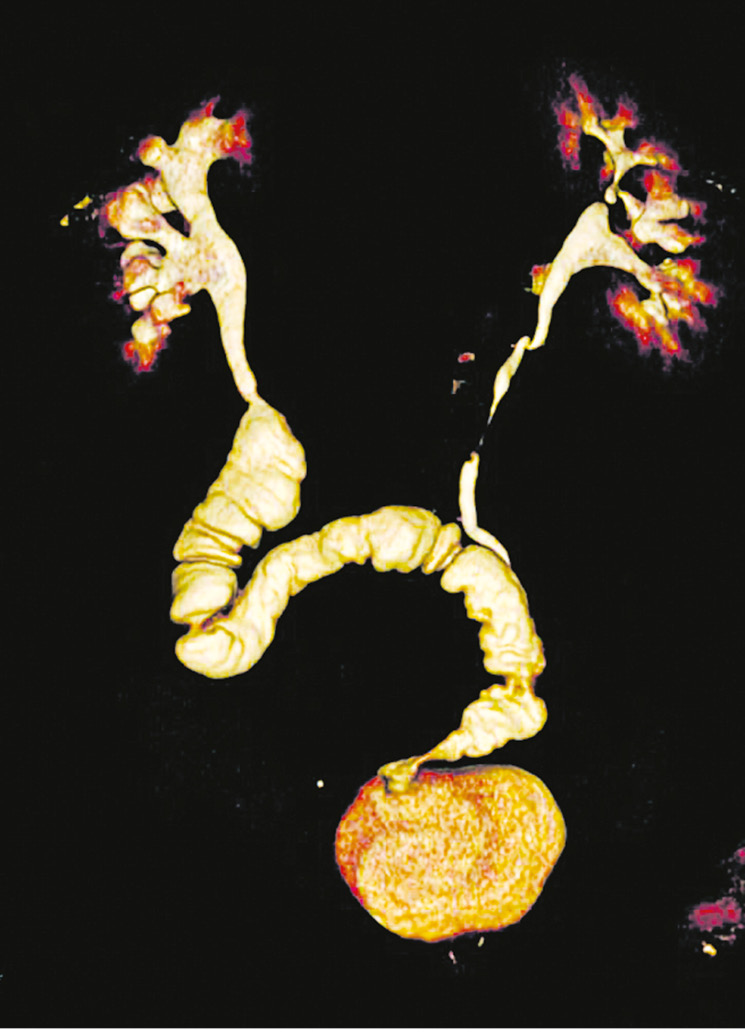

Bilateral small intestinal reconstruction of the ureters was performed in 40 (20.7%) patients. Most often, in 24 (60.0%) patients, U-shaped ileoureteroplasty was performed (Figs. 8 and 9), and more complex reconstructions were performed less often; that is, Y-shaped in 1 (2.5%) case, J-shaped in 3 (7.5%), L- and 7-shaped (Figs. 10 and 11) ileoureteroplasty in 6 (15.0%), and that with two separate ileografts in 6 (15.0%) cases.

Fig. 10. Bilateral isoperistaltic 7-shaped ileoureteroplasty

Fig. 11. Multisection computed tomography (MSCT) with contrasts of the patient 5 years after bilateral isoperistaltic 7-shaped ileoureteroplasty